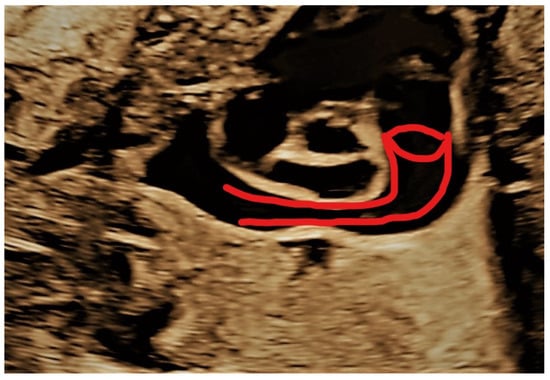

4.2. Case 2